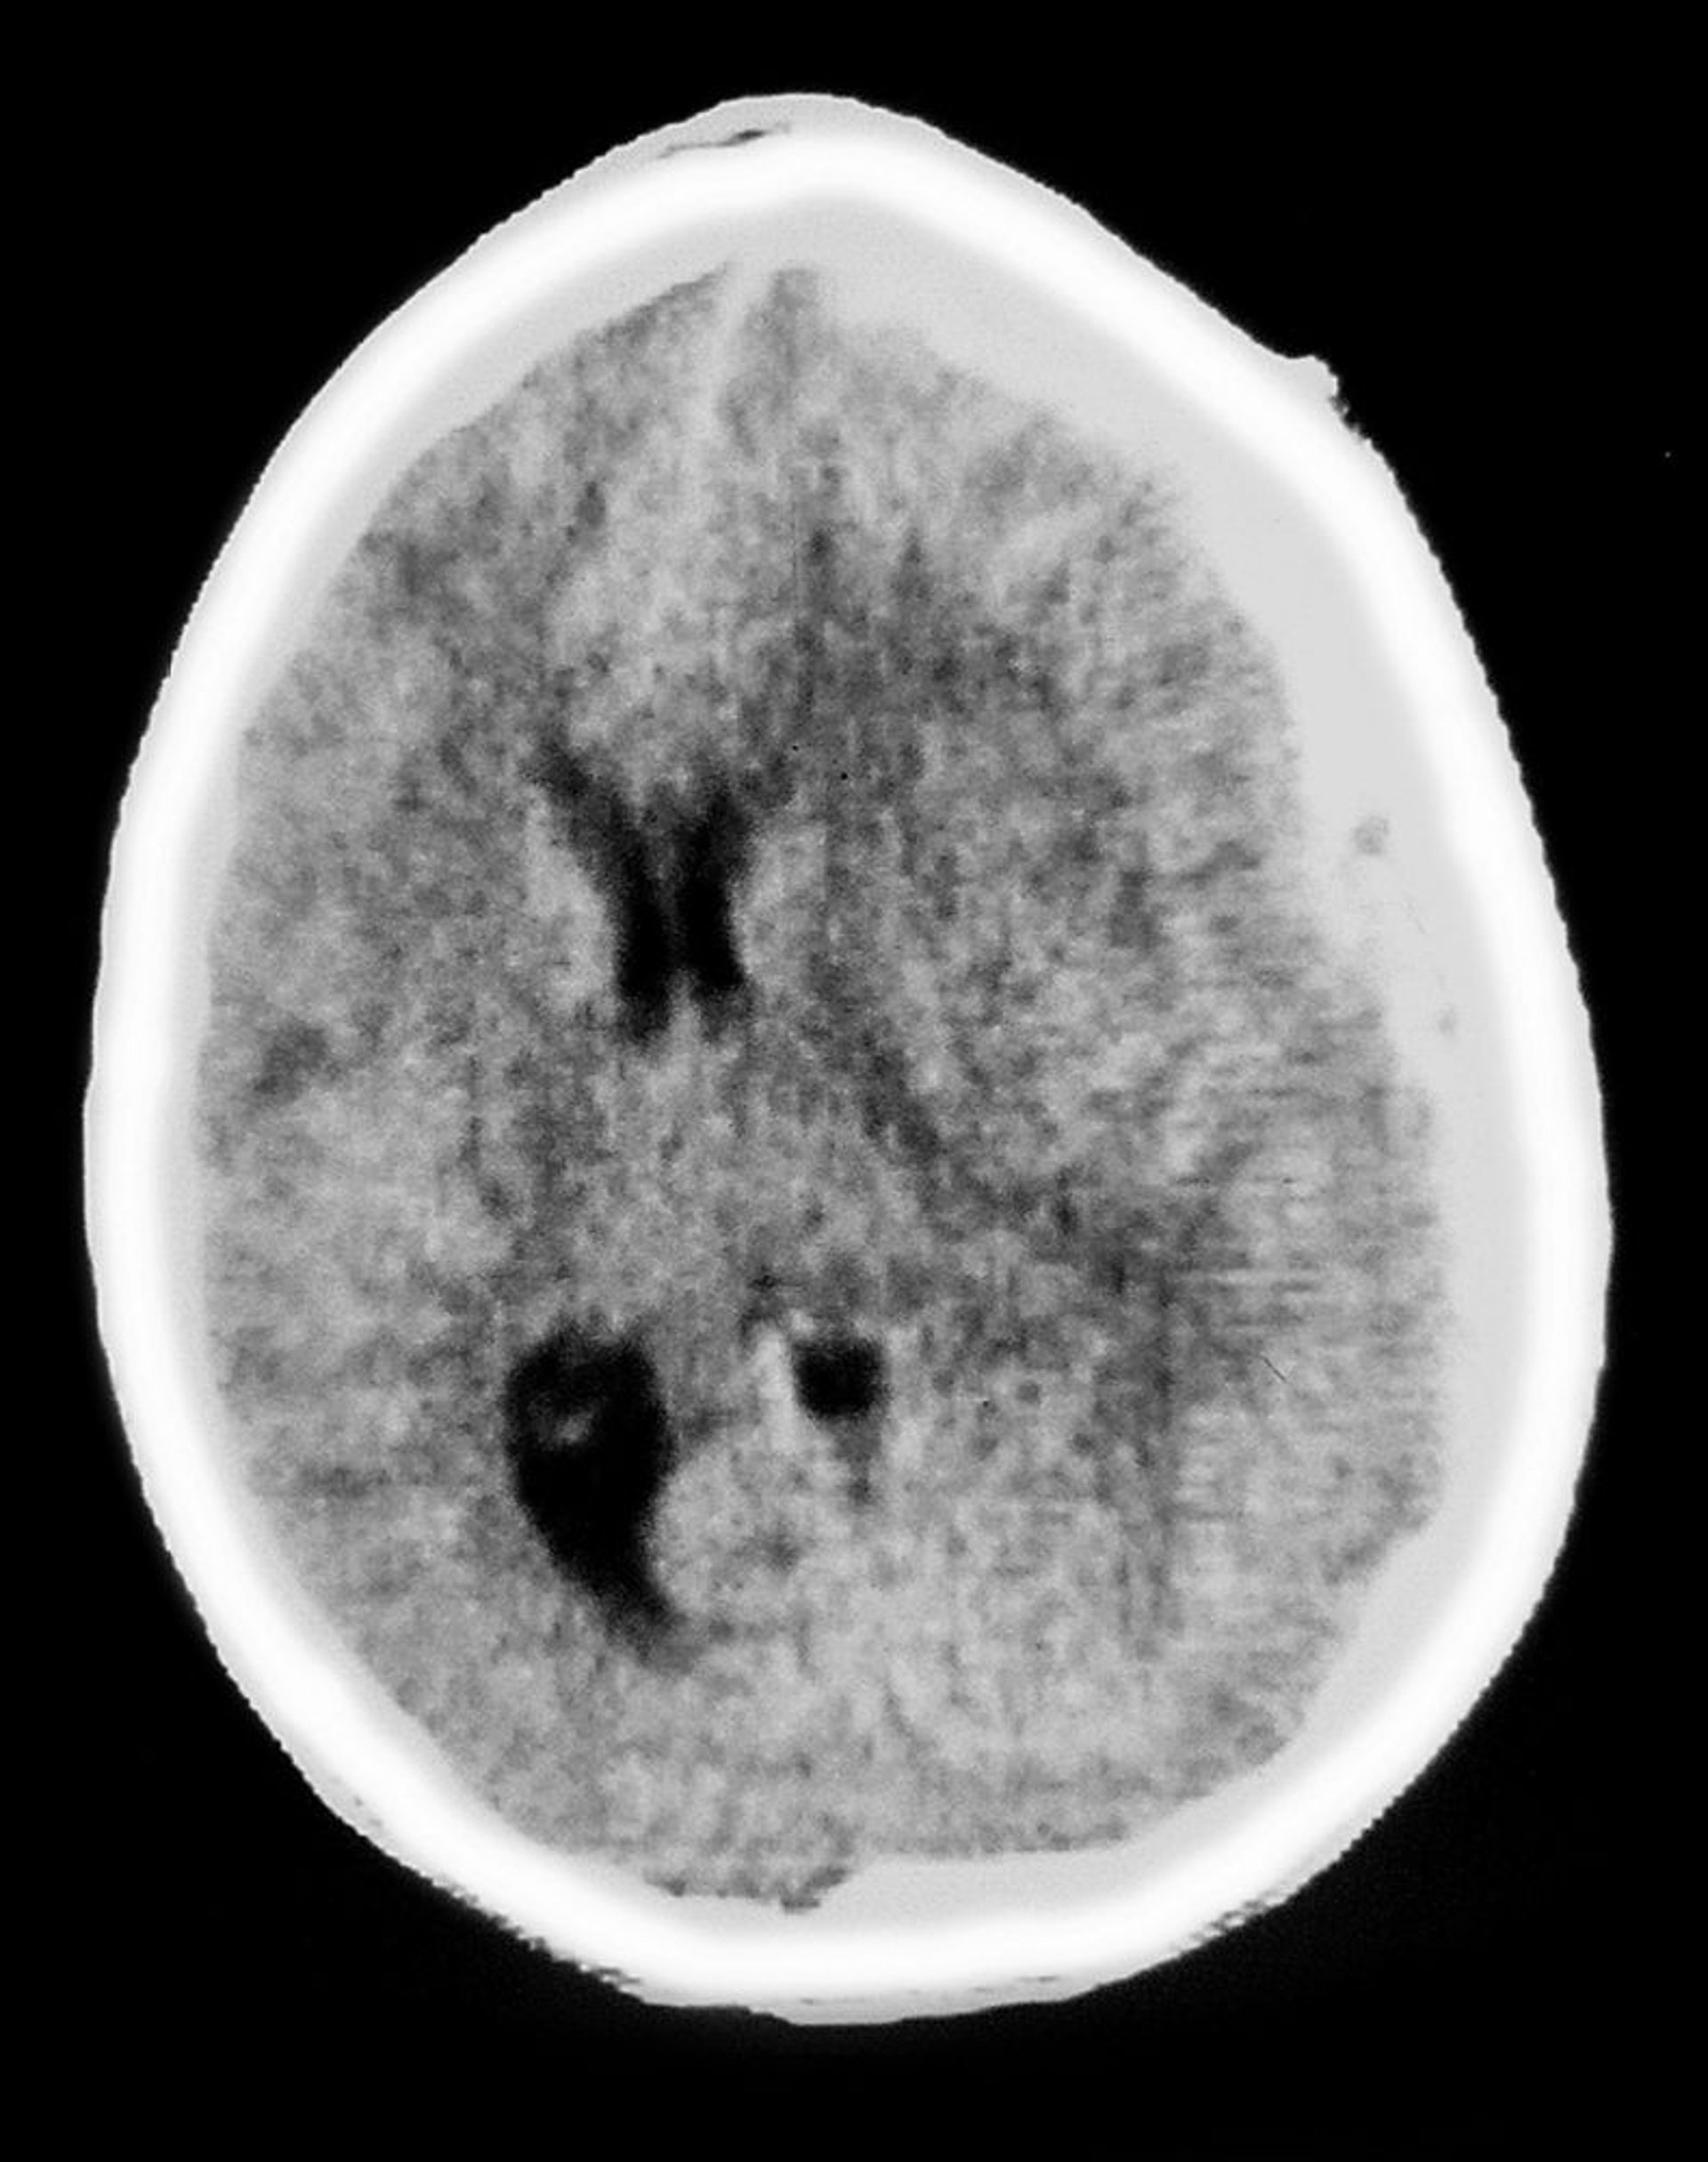

Hematoma subdural

Essa CT mostra opacidade em forma de lua crescente recobrindo o tecido cerebral, característica de hematoma subdural. Há também efeito de massa, com compressão ventricular e desvio da linha média.